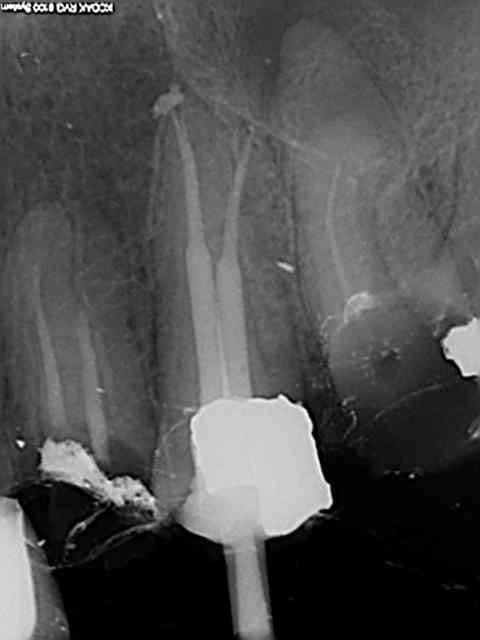

Et une de plus !

R19 vxiysf - Eugenol

R20 kboz6l - Eugenol

01 ukhwbq - Eugenol

C'est pas de la frime hein, mais ca fait plaisir d'avoir trouvé ENFIN une technique rapide et reproductible sans casse. (enfin presque il y a dans le tas un micro morceau de R25 pas loin de l'apex )